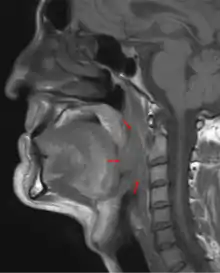

Oropharyngeal cancer (OPC),[1][2][3] also known as oropharyngeal squamous cell carcinoma (OPSCC) and tonsil cancer,[1] is a disease in which abnormal cells with the potential to both grow locally and spread to other parts of the body are found in the oral cavity, in the tissue of the part of the throat (oropharynx) that includes the base of the tongue, the tonsils, the soft palate, and the walls of the pharynx.[1][2][3][5]

| 3D medical illustration showing the cancer formation in the tissues of the oropharynx | |